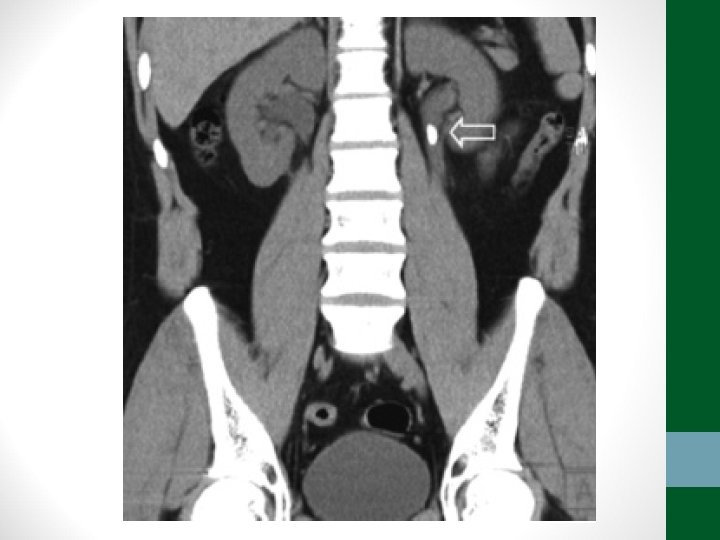

Exames de Imagem • Abdome Agudo Vascular: • Radiografia simples de abdome: decúbito, ortostase e cúpulas diafragmáticas • USG abdome não ajuda! • TC Abdome com contraste EV e VO – angio. TC (fase arterial e portal) é o melhor exame

Exames de Imagem • Abdome Agudo Hemorrágico: • Radiografia simples de abdome: decúbito, ortostase e cúpulas diafragmáticas (apenas para descartar outras causas) • USG Abdome é o exame mais importante, pode ser necessária USG transvaginal • TC de Abdome em casos selecionados